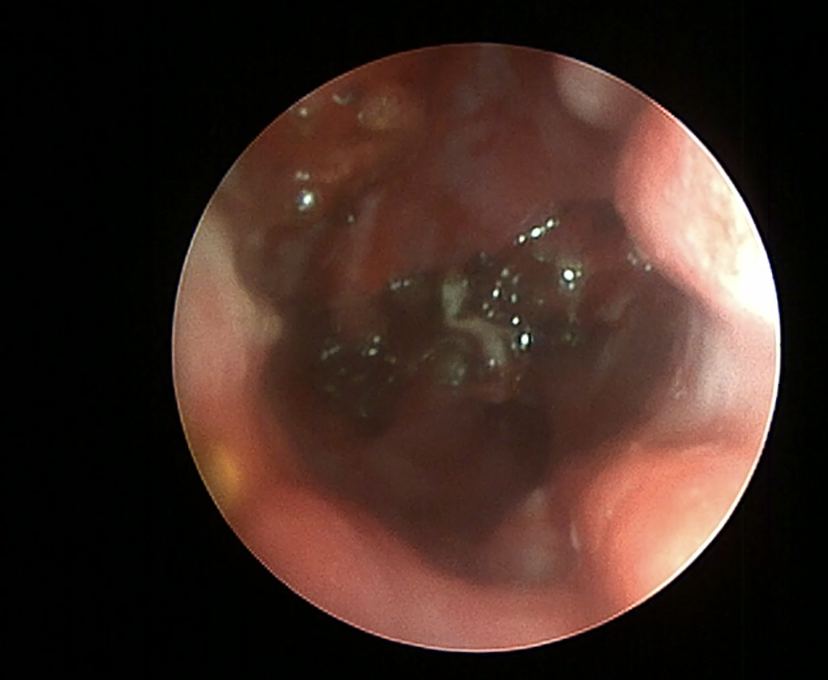

Mittels dualem Diodenlaser lässt sich das Blutungsrisiko von Lasereingriffen minimieren, beispielsweise auch die Resektion der Concha nasalis ventralis (CNV). Dieser Eingriff erfolgt in Anlehnung an Oechtering et al. (2016). Es beginnt mit einer Schleimhautinzision der Basallaminia der CNV mit 10 W 1470 nm. Die weitere Abtragung der CNV erfolgt dann im dualen Modus (3 Watt, 980 nm plus 6 – 10 Watt 1470 nm). Der Eingriff erfolgt im Dauermodus (cw) mit einer 400 µm – Faser (Abb. 2).